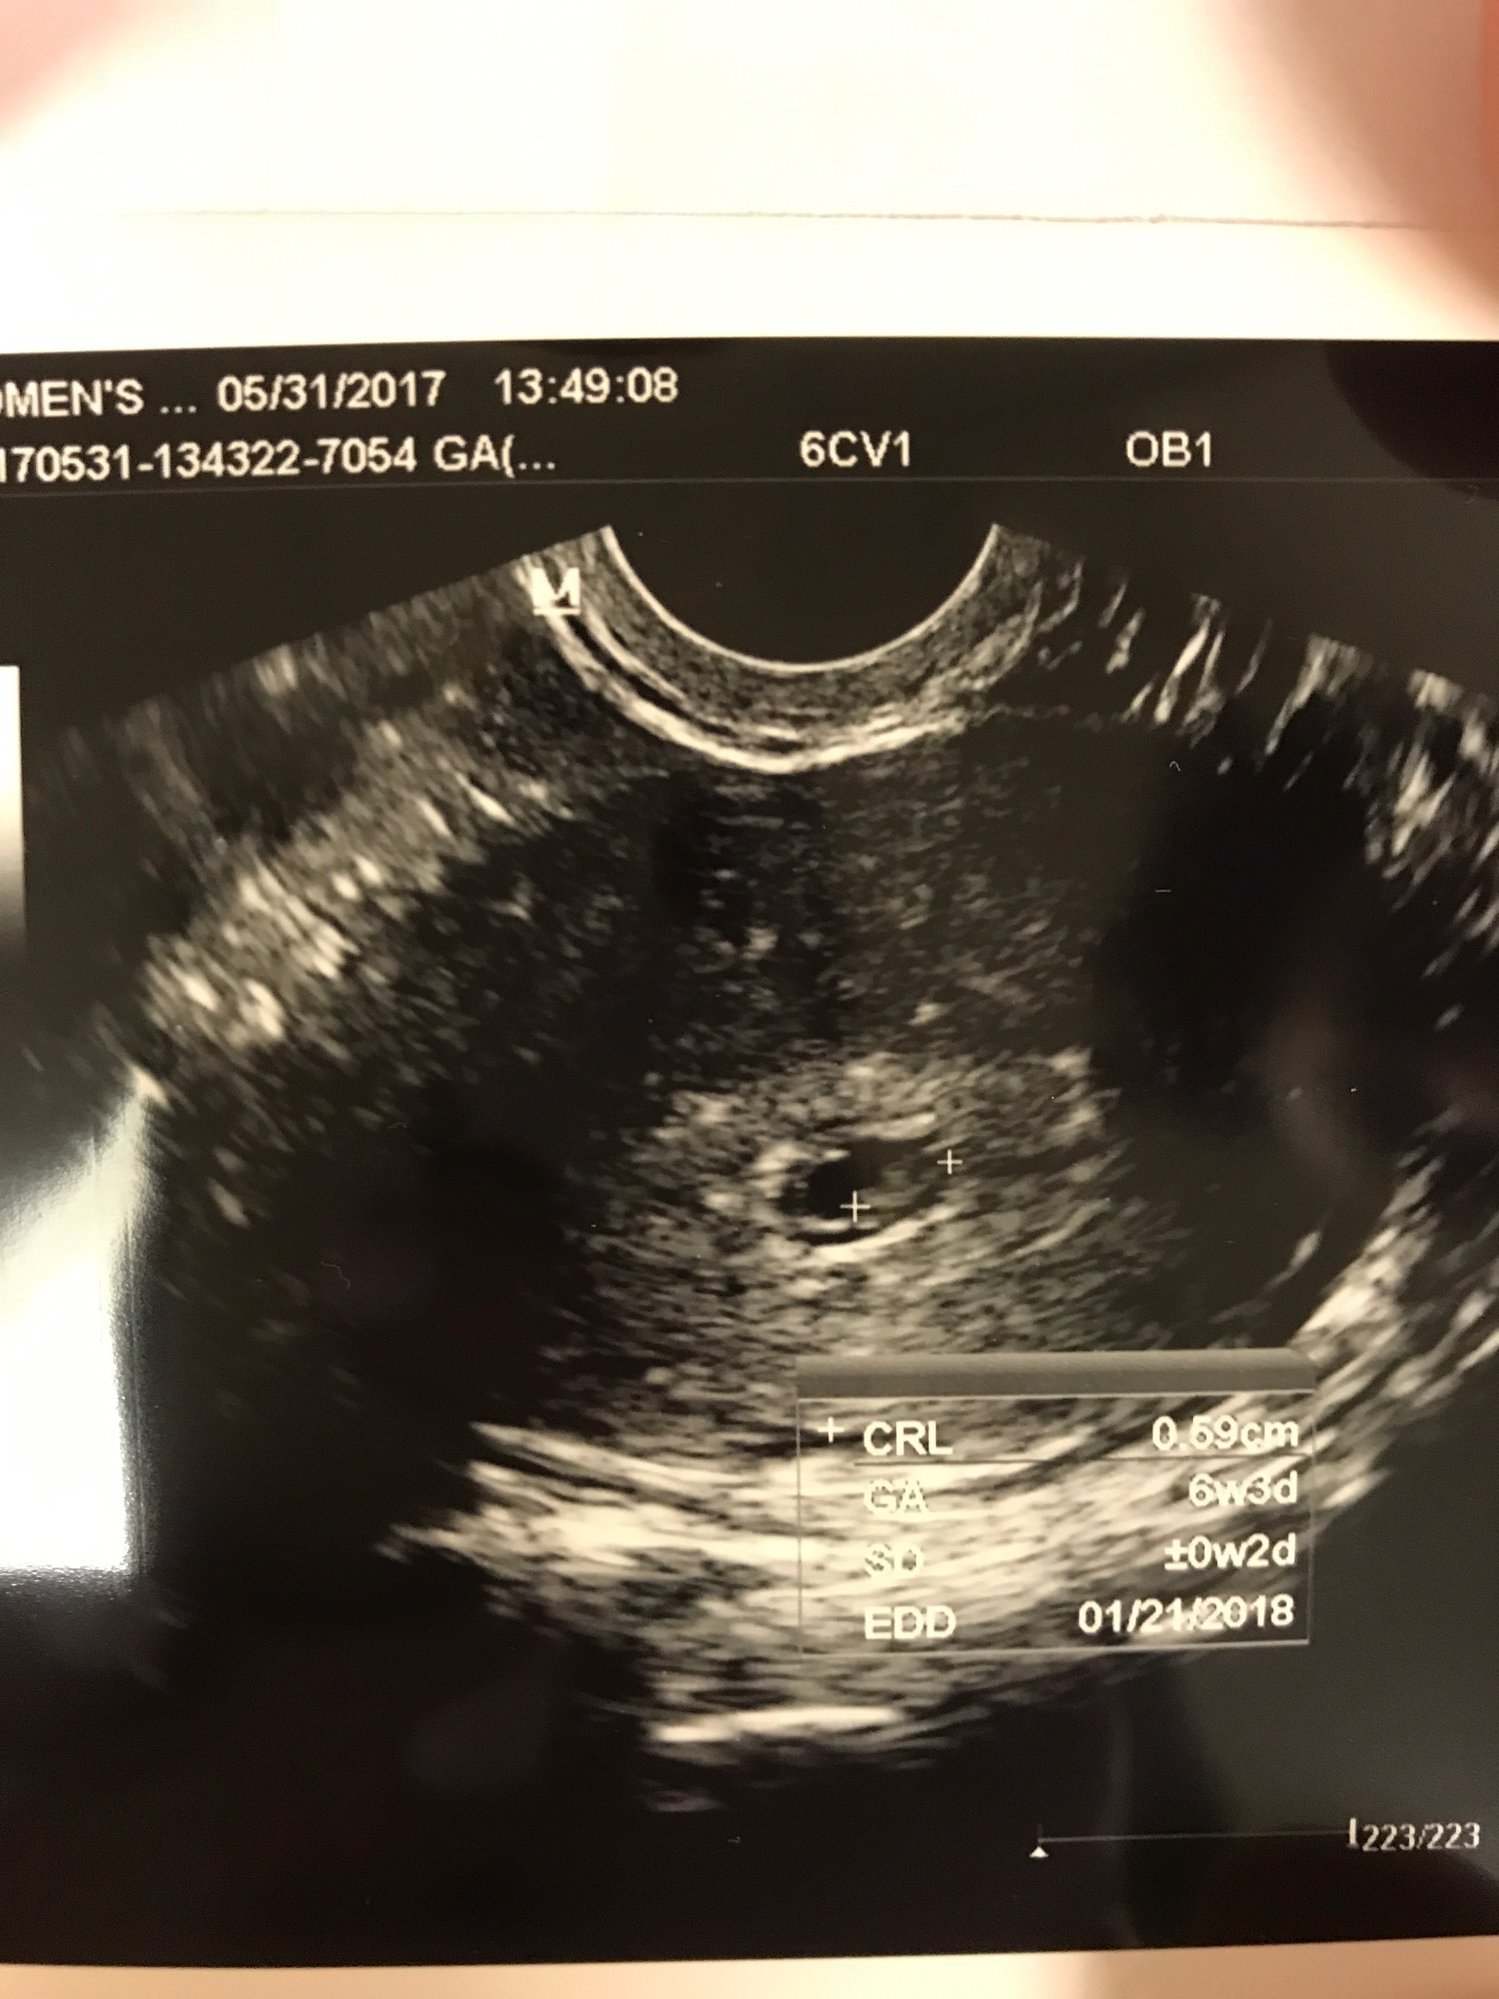

Happy to report that ultrasound looked normal, due date stayed the same, 6w+5d & Jan. 21 EDD. Going back in about a week for another ultrasound and some blood work. This is the best pic she could get (damn tilted uterus!). DH wasn't allowed back with me until the very end and we just got to see this on the screen. We saw a fluttering heartbeat but that's it. I was told it was too soon and dangerous to do a doppler

Happy to report that ultrasound looked normal, due date stayed the same, 6w+5d & Jan. 21 EDD. Going back in about a week for another ultrasound and some blood work. This is the best pic she could get (damn tilted uterus!).

DH wasn't allowed back with me until the very end and we just got to see this on the screen. We saw a fluttering heartbeat but that's it. I was told it was too soon and dangerous to do a doppler